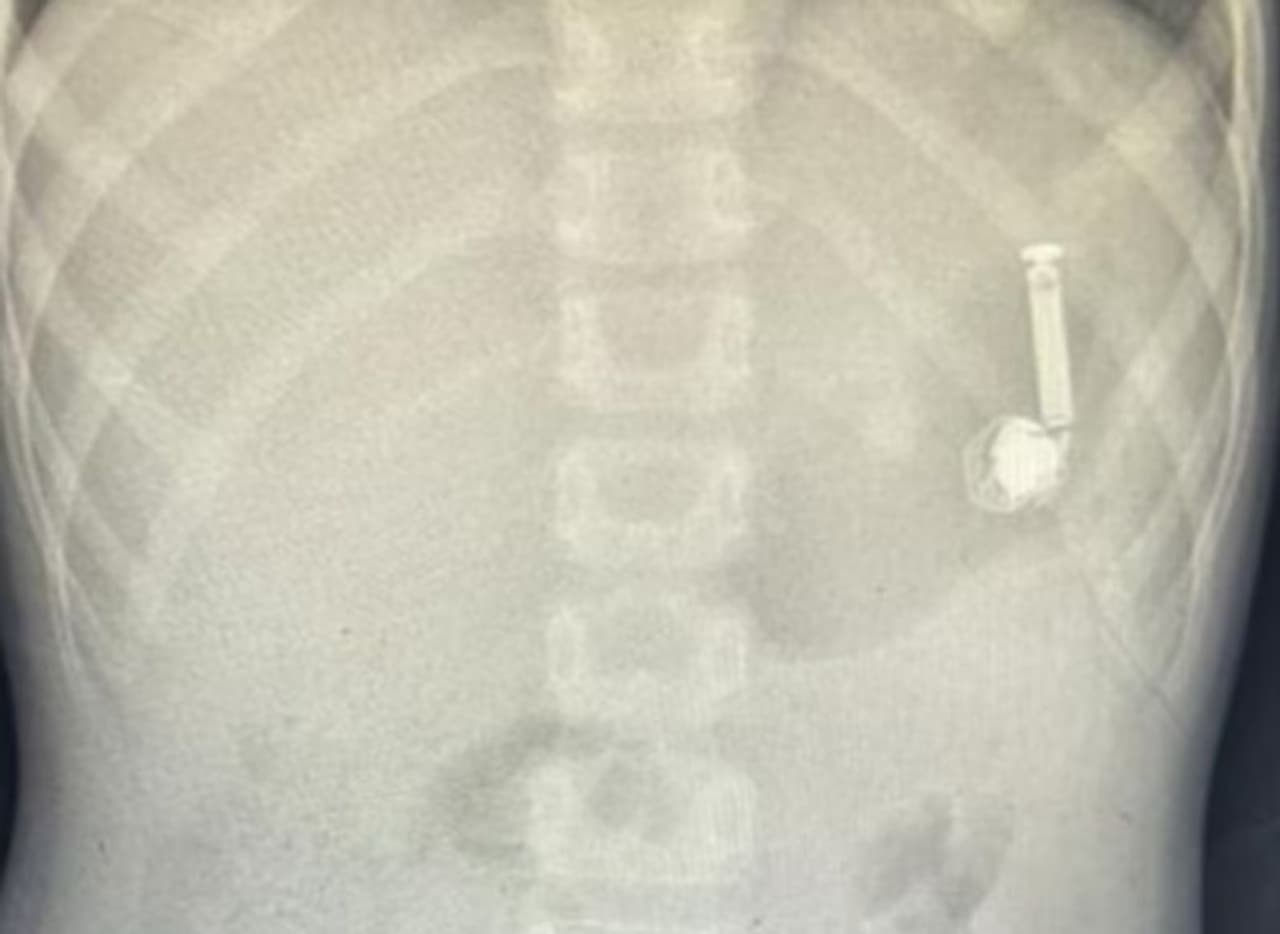

ആവശ്യമായ വൈദ്യപരിശോധനകളും എക്സ്റേ പരിശോധനയും നടത്തി. എന്ഡോസ്കോപ്പി വിഭാഗത്തില് നിന്നും അനസ്തേഷ്യ വിഭാഗത്തില് നിന്നും മെഡിക്കല് ടീമിനെ രൂപീകരിച്ച് കുട്ടിയെ എന്ഡോസ്കോപ്പിക്ക് സജ്ജമാക്കി. ശേഷം ലാപ്രോസ്കോപ്പി വഴി ഇയര് ബഡ് പുറത്തെടുക്കുകയായിരുന്നു.